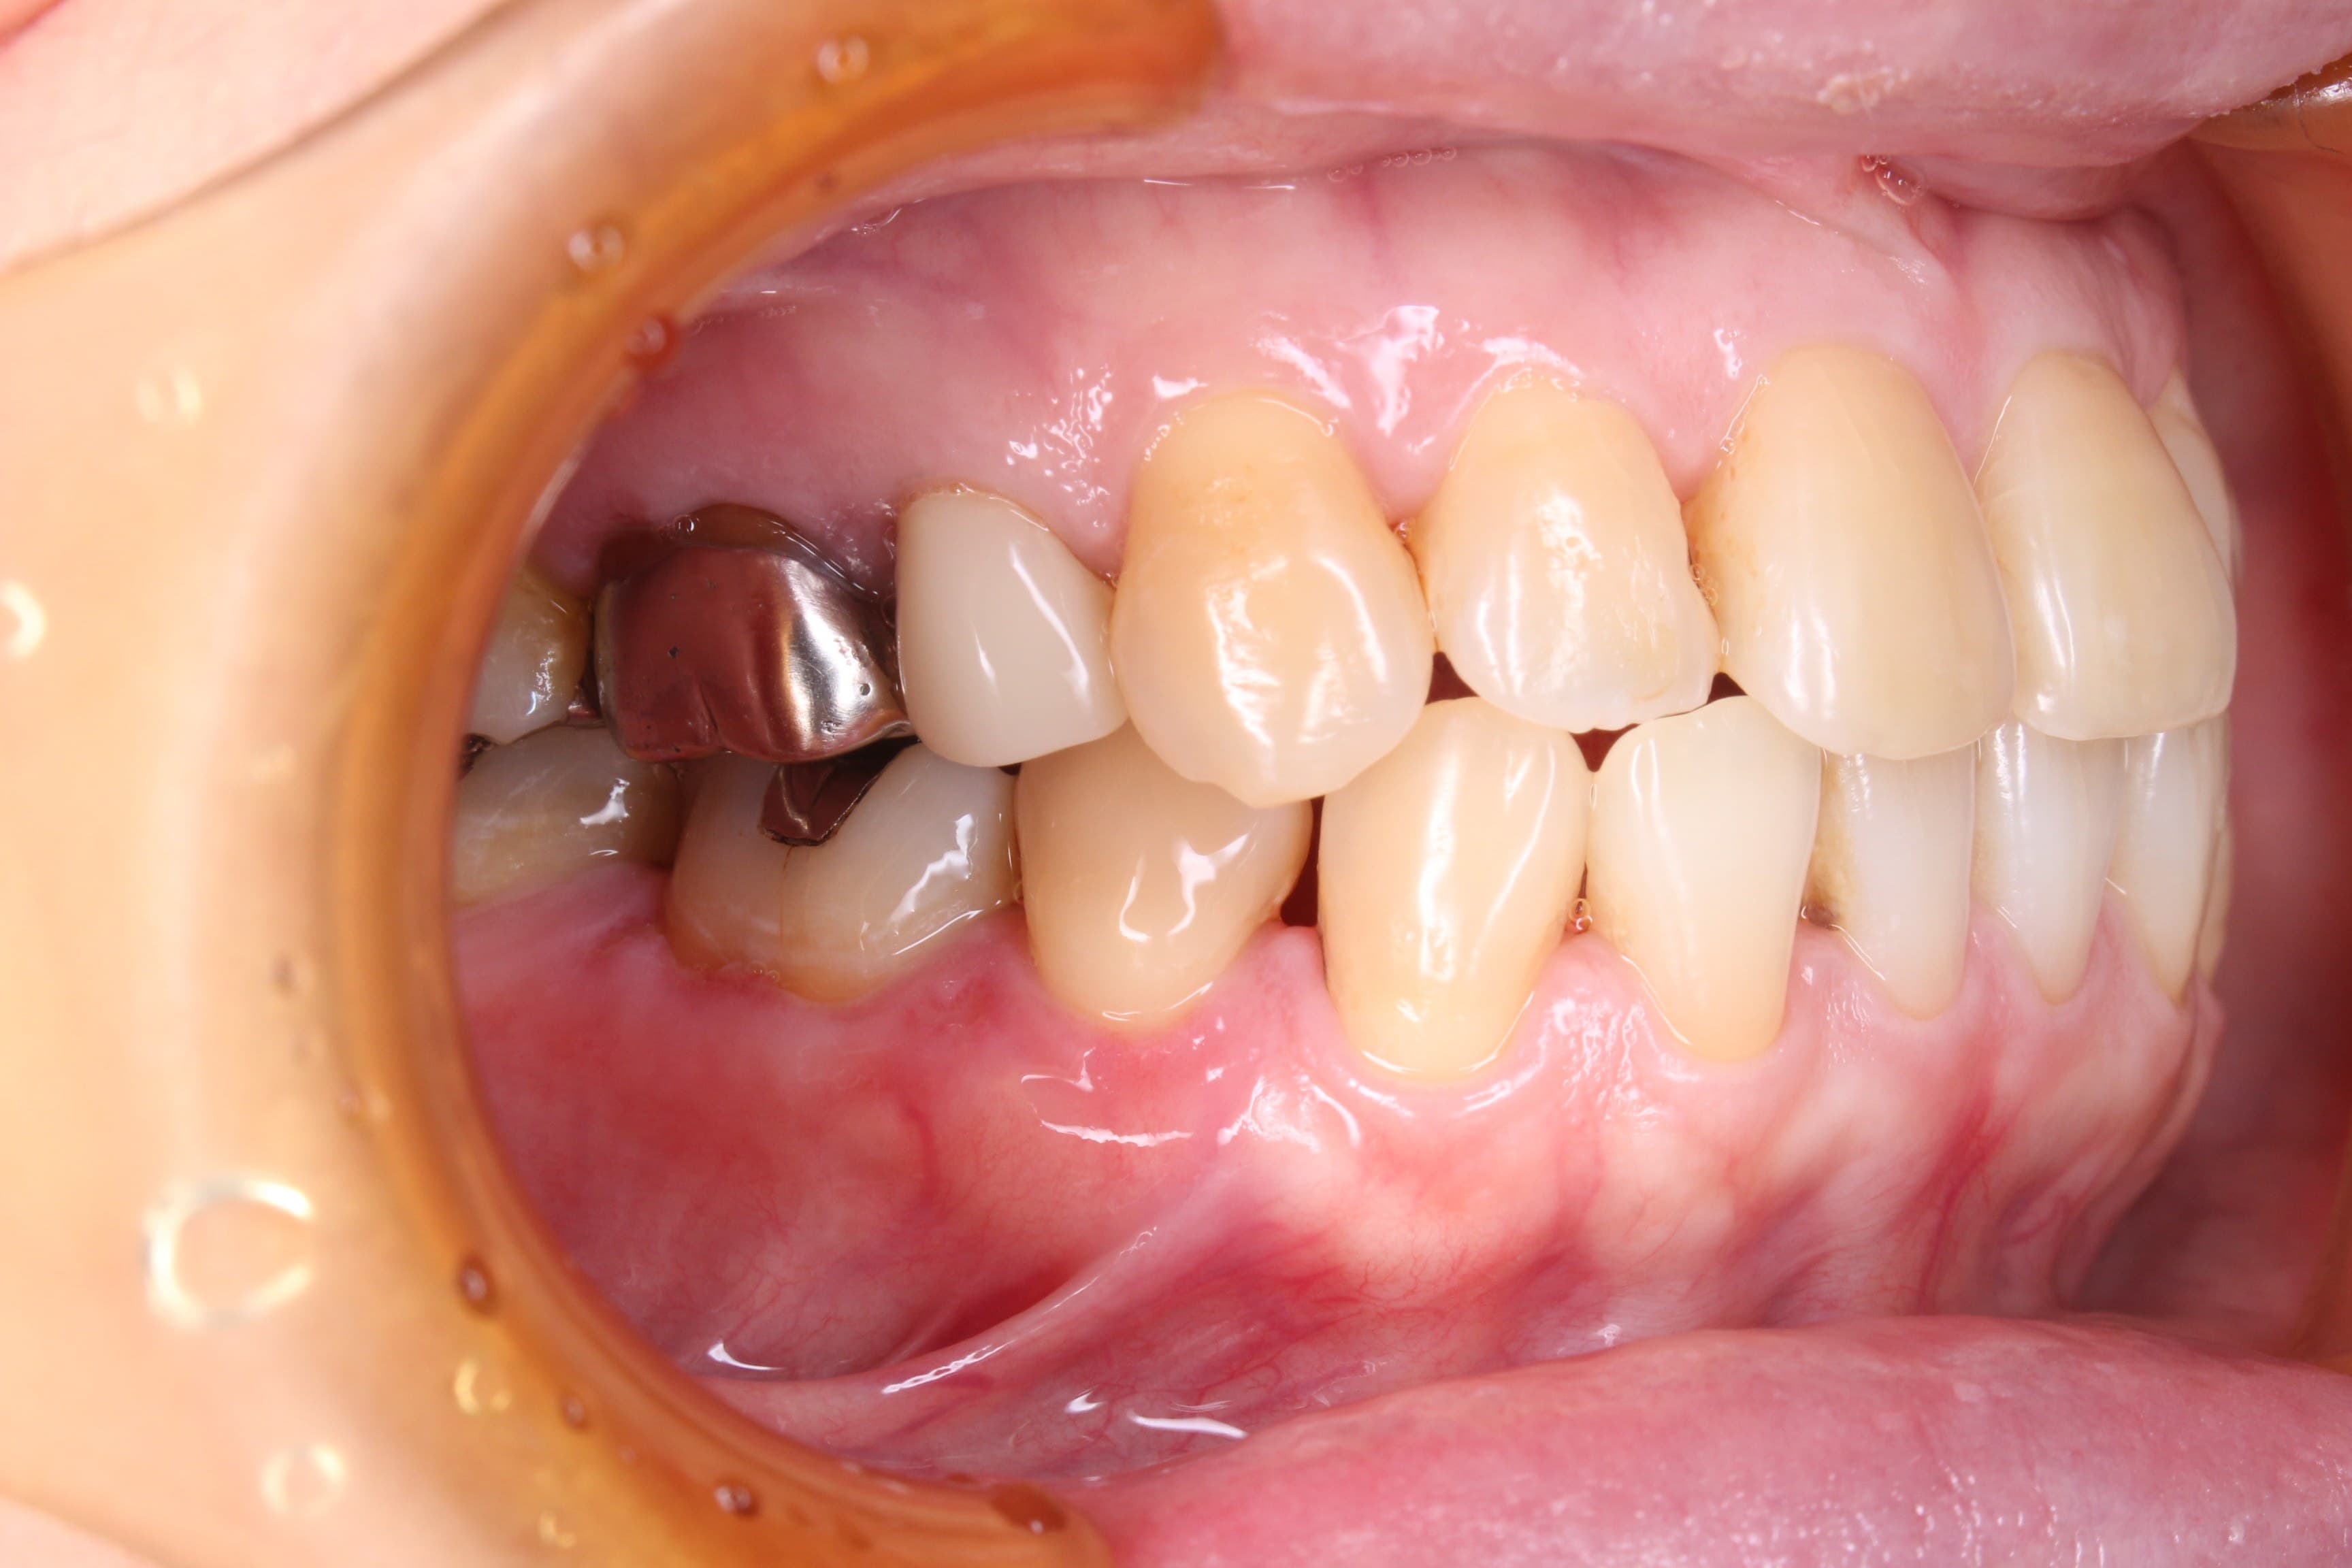

今回ご紹介する歯周専門治療のケースは、60代女性の方です。

50代から長期間身体を壊し、他院にて6か月に1度歯石取り(メンテナンス?)を行っていましたが、一向に口腔内のネバネバや不快感が改善しなかった為、来院されました。

基本検査の結果、全体的に中程度の歯周ポケットがあり、歯肉からの出血、歯周ポケット内に歯石を確認することができました。

またお手入れは、ご自身では見え難いところに磨き残しがありました。

治療前